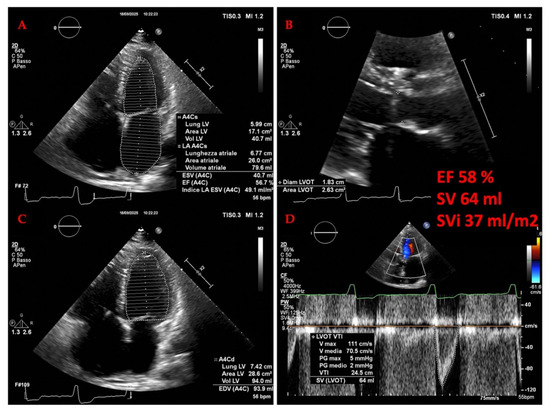

Background: Transthoracic echocardiography (TTE) is the primary imaging modality to assess cardiac morphology and function. In athletes, distinguishing physiological adaptations from pathological changes is essential. This study aimed to evaluate long-term cardiac structural and functional changes in professional soccer players. Methods: This retrospective [...] Read more.

Background: Transthoracic echocardiography (TTE) is the primary imaging modality to assess cardiac morphology and function. In athletes, distinguishing physiological adaptations from pathological changes is essential. This study aimed to evaluate long-term cardiac structural and functional changes in professional soccer players. Methods: This retrospective study included 20 healthy male professional soccer players (mean age 21.2 ± 3.4 years) from the German first division, examined annually from 2016 to 2024 (mean follow-up 5.6 ± 2.0 years). TTE parameters associated with the “athlete’s heart” were assessed, including left ventricular end-diastolic diameter (LVEDD), interventricular septal thickness (IVSD), relative wall thickness (RWT), indexed LV mass (LVMi), and left atrial volume index (LAVi), along with 3D-derived LV and RV volumes. Advanced deformation imaging included global longitudinal strain (GLS), right ventricular strain (RVS), and left/right atrial reservoir strain (LASr and RASr, respectively). Baseline and final follow-up values were compared. Results: No significant changes were observed over time in conventional or advanced echocardiographic parameters (e.g., LVEDD: 54.5 ± 3.1 mm vs. 54.6 ± 3.9 mm; p = 0.868; GLS: −18.7% ± 2.2% vs. −18.4% ± 1.9%; p = 0.670). Ventricular volumes and strain values also remained stable throughout follow-up. Conclusions: Over a mean follow-up of more than five years, professional soccer players showed stable cardiac morphology and function without evidence of pathological remodeling. These findings support the concept that long-term high-level training in mixed-discipline sports leads to balanced, physiological cardiac adaptation. Full article

Figure 1